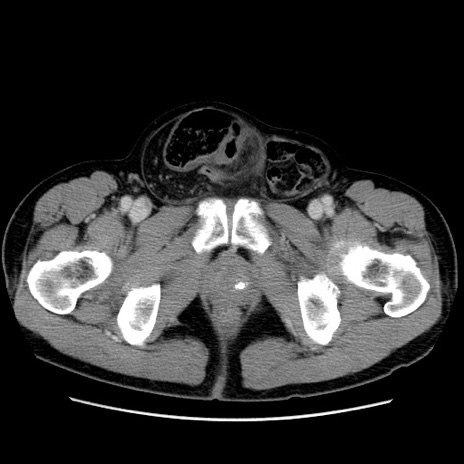

症例34(横断像)

【主訴】右鼠径部膨隆

【現病歴】1年程前より右鼠径部膨隆あり。自己にて還納可能だったため放置していた。3時間前より右鼠径部の脱出を認め、還納困難となり受診。

【身体所見】右鼠径部に小児頭大の膨隆あり。弾性硬であり、用手還納は困難。左鼠径部にも膨隆を認める。脱出はなし。